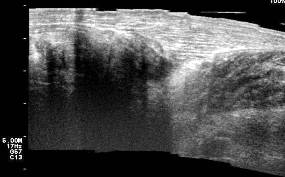

Ultrasonido articular y partes blandas, observándose imagen compleja en proyección de los músculos gastronemios con zonas solidas que alternan con imágenes quísticas tabicadas. Imágenes 5, 6 y 7

Imagen 5. Ultrasonido articular con imagen compleja

Imagen 6. Ultrasonido articular y partes blandas con zonas solidas que alternan con imágenes quísticas tabicadas